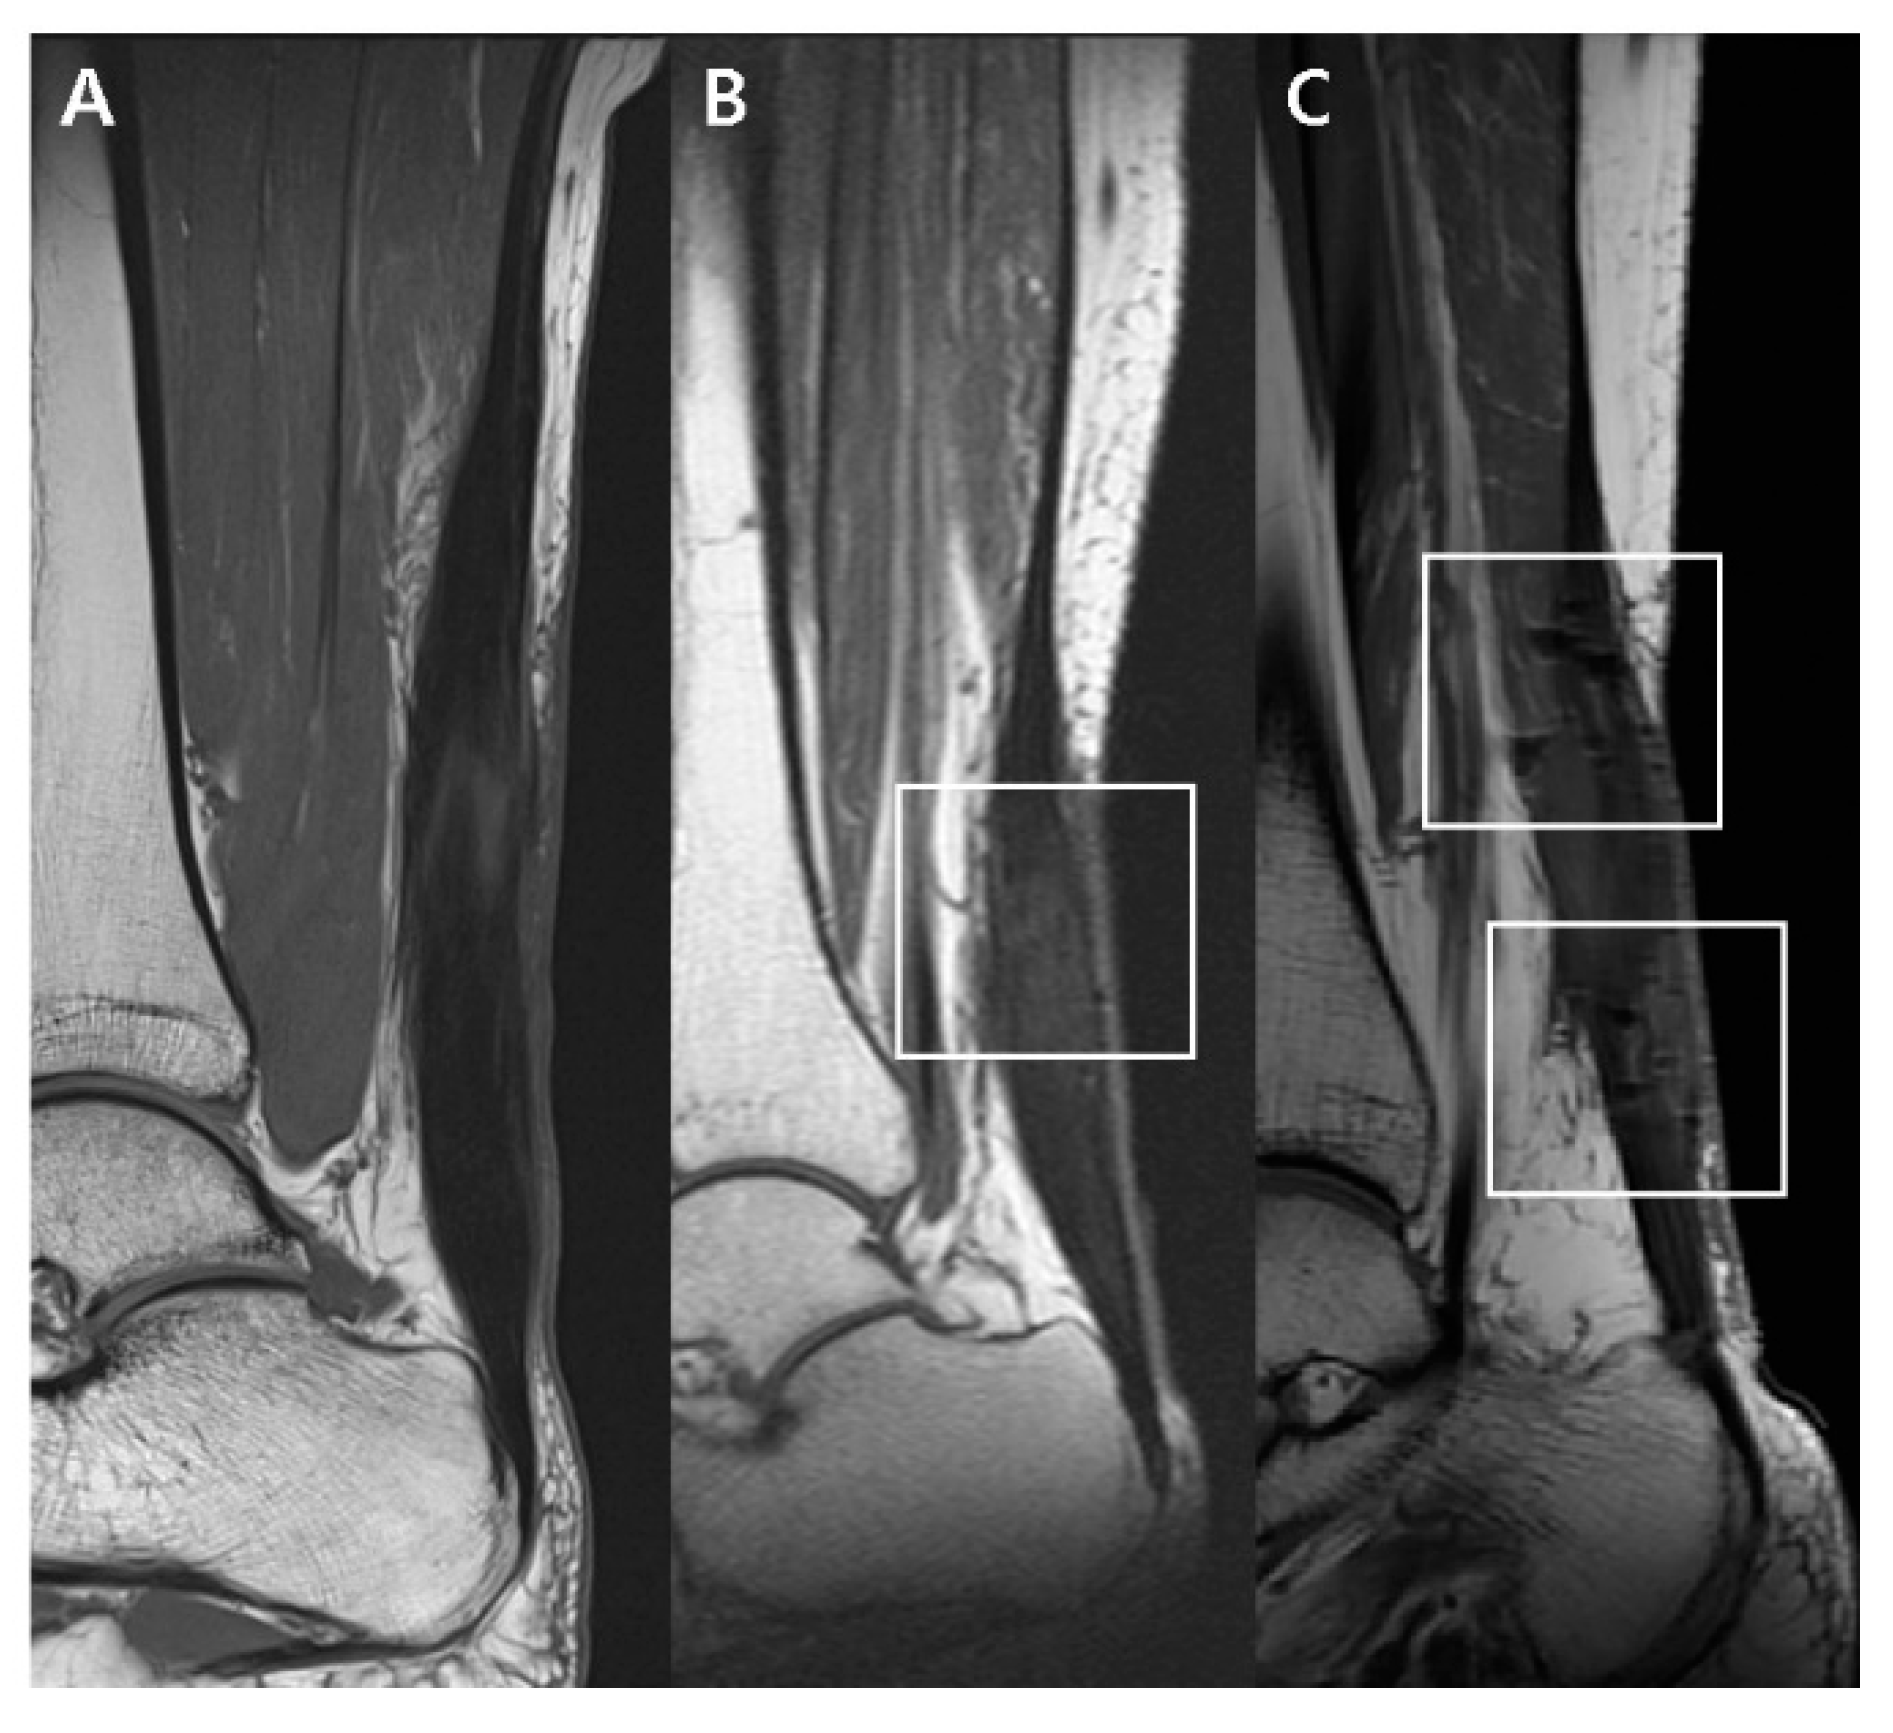

2.5.1. T1-Weighted Sagittal Image

| Dark SI artifact | 0.0063 | ||

| None | 3 (27.27%) | 0 (0%) | |

| Mild | 8 (72.73%) | 5 (45.5%) | |

| Marked | 0 (0%) | 6 (54.5%) | |